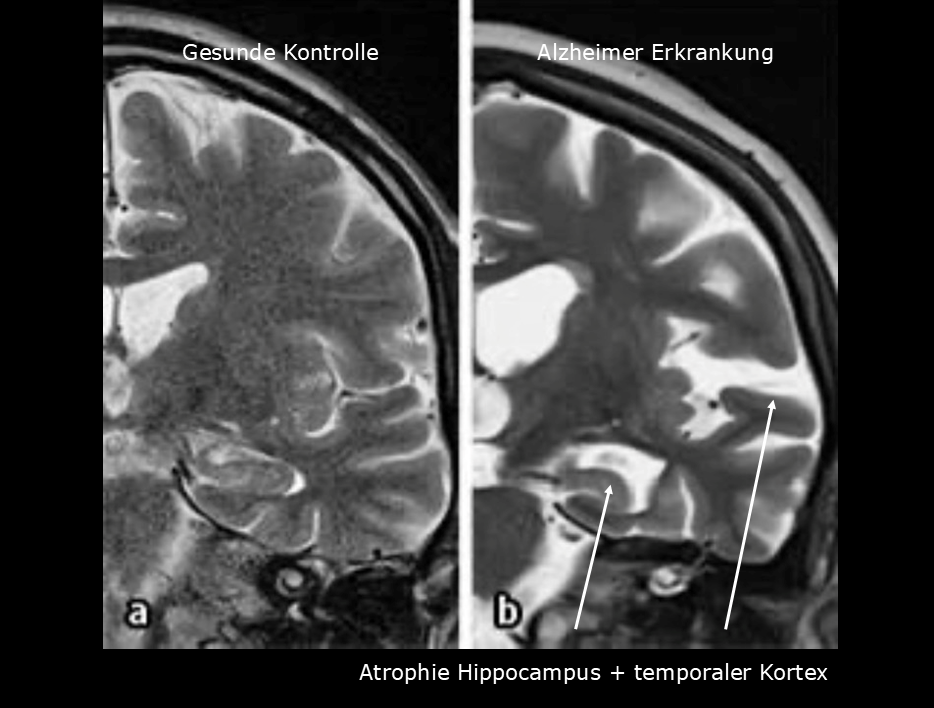

Für die Diagnosestellung sind ärztliche Gespräche, Untersuchungen, neuropsychologische Tests und bildgebende Verfahren erforderlich. Moderne Verfahren wie Biomarker-Analysen spielen nach aktuellen Leitlinien eine wachsende Rolle, um Krankheitsursachen frühzeitig und möglichst präzise zu erkennen. Aktuell können dafür bestimmte Eiweiße im Nervenwasser untersucht werden, Bluttests werden noch nicht allgemein empfohlen.